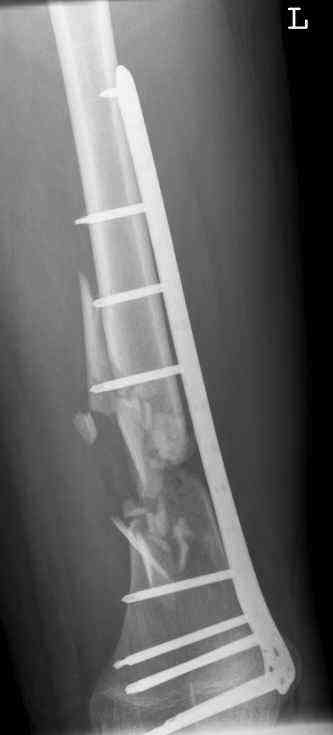

nov 07: persistant non-union distal femur; other fractures healed uneventfully.

All with gradual/partial weightbearing etc. Currently 50-100% weight bearing, no pain.

Soft tissues are intact. No smoking or diabetes.CRP <2

What would you do?

This is a true atrophic pseudoartrosis (without pain).

This fracture have a two factors failure combination.

The mechanical factor failure and the biological factor failure.

The solution need a combination of treatments which give solutions for each factor failure.